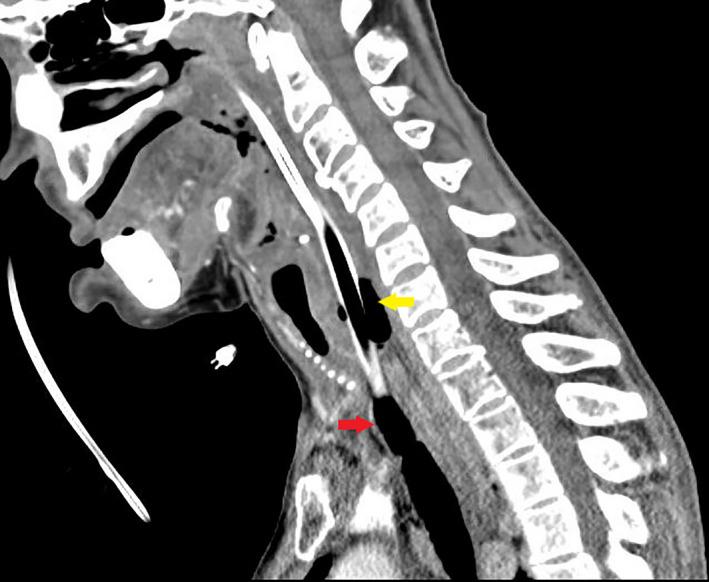

Iatrogenic tracheoesophageal fistula (TEF) through direct penetration of esophageal and tracheal walls is exceedingly rare. Body tissues sealing around the tube may result in delayed development of respiratory complications and diagnosis. Pneumomediastinum and pneumothorax may be absent. Maintaining the airway through TEF until tracheostomy resulted in a satisfactory outcome.